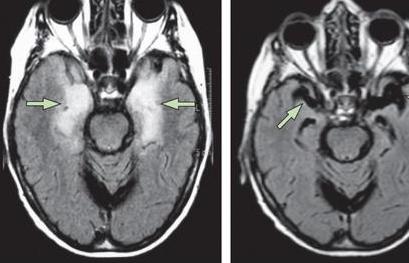

脑炎后遗症的出现对于患者的影响是很大的,对于每位脑炎后遗症患者来说,及时的接受正规专业的治疗是很关键的,也是很重要的,目前,治疗脑炎后遗症的方法是很多的,常见的方法包括免疫疗法、推拿疗法、对症治疗以及抗病毒治疗,这几种治疗方法的效果都是很不错的,下面我们就来进行一下详细的介绍,希望可以帮到大家。

免疫疗法治疗脑炎后遗症:血清疗法,起病3天内患者可用恢复期患者或林区居住多年者的血清20~40ml肌注,或椎管内注射5~10ml。高效价免疫丙种球蛋白每日6~9ml肌注,至体温降至38℃以下停用。干扰素、转移因子、免疫核糖核酸,核糖核酸酶均可酌情采用。

抗病毒治疗脑炎后遗症:脑炎后遗症患者应该使用抗病毒治疗,虽然目前尚无有效的抗病毒药物,但以下药物可以使用,碘甙(疱疹净)、三氮唑核苷(病毒唑)、丙种球蛋白,其他如转移因子,干扰素可以提高机体对病毒的抵抗能力,均可应用。